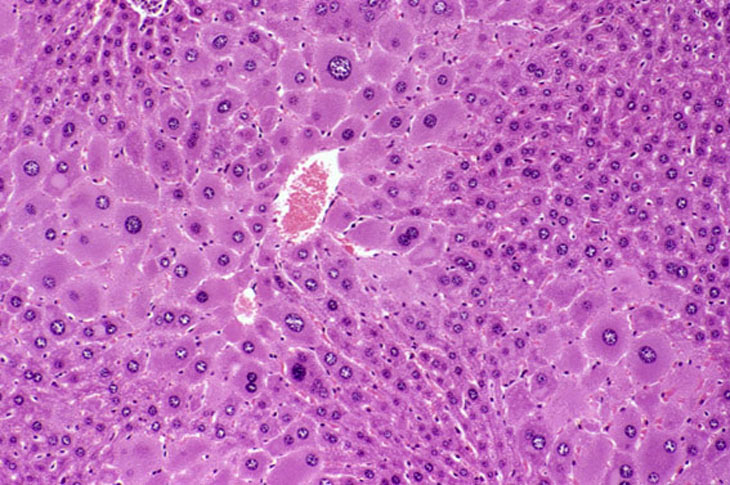

Generalized hepatocyte hypertrophy involving all portions of the hepatic lobule. Higher magnification shows a cytomegalic hepatocyte in the lower right. It has an enlarged nucleus with multiple nucleoli.

Hypertrophic and cytomegalic hepatocytes are present in the centrilobular and midlobular areas in these images from a mouse treated with chlordane for several months. Some cytomegalic hepatocytes have several nuclei.